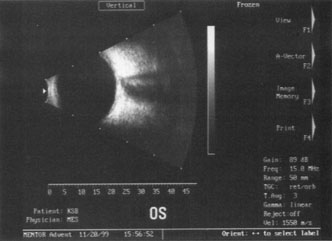

ENDOTHELIAL CELL COUNT.

Although slit-lamp examination can give the ophthalmologist an excellent estimate of endothelial health, sometimes a formal assessment of the corneal endothelial cell density is helpful (Fig. 4). This information is most likely to be helpful in advising patients who may be at greater risk of postoperative corneal decompensation. Specifically, patients with cornea guttata, previous ocular surgery, history of blunt ocular injury,56 exfoliation syndrome,57 iridocorneal-endothelial syndromes,58 or a history of glaucoma59 are known to have reduced endothelial cell counts. Patients with a history of acute angle closure are at particular risk because each episode of elevated intraocular pressure can damage endothelial cells.60

Fig. 4. A noncontact endothelial cell photograph demonstrates a normal cell mosaic and density. The cell count is calculated by identifying those cells within the box and touching two of the four adjacent edges.

There are qualitative and quantitative methods for endothelial cell evaluation. Cell density can be measured directly with an endothelial cell camera. The surgeon also should view the photograph and qualitatively estimate the regularity of the endothelial cell mosaic. Some instruments calculate a coefficient of variability and percent of hexagonal cells.